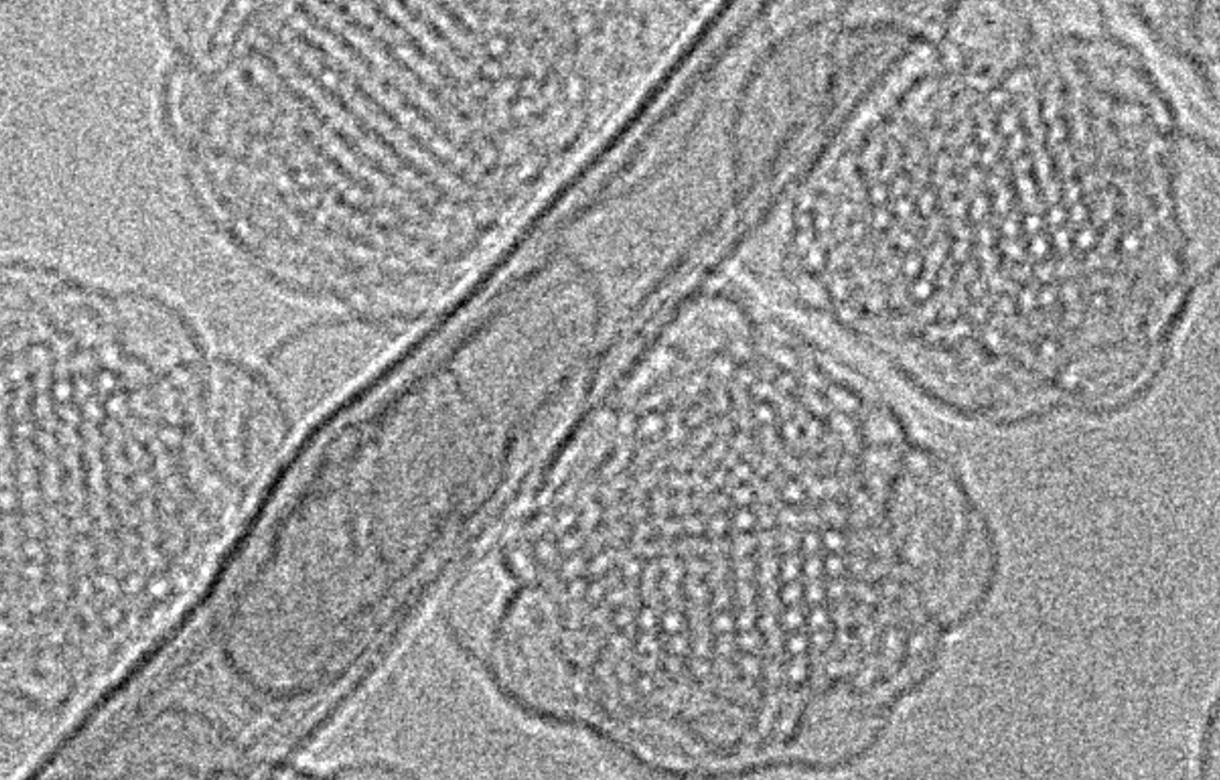

These nanoparticles have different internal structures such as layers (liposomes) or more complex 3D cubic shapes (cubosomes), with researchers discovering that these shapes have a big impact on what pathways they take to enter cells.

Cubosomes are tiny nanoscale particles formulated from the self-assembly of lipids in water. The lipids self-assemble into an intricate and complex 3D cubic structure, with water channels and lipid bridges running throughout the entire particle that can be used to package small molecule drugs.

In vitro tests using an epithelial cell line found cubosomes were the most efficient at entering cells.

The study revealed cubosomes were eight times more likely to enter the cells than liposomes, which are what most lipid-based nanomedicines and commercial products use today.

Cubosome